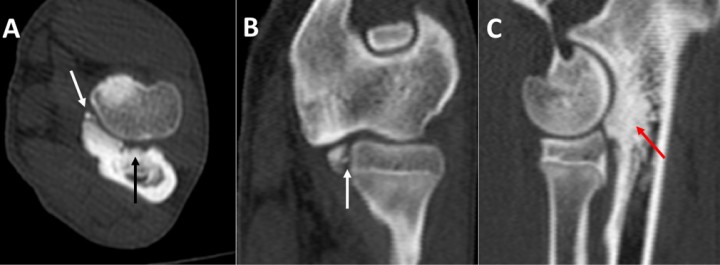

De los 66 codos estudiados 53 fueron positivos al diagnóstico de EACM en forma de: fragmentaciones (41 codos), fisuras (8 codos), esclerosis (3 codos) y osteomalacia (1 codo) (Fig. 1). La fragmentación se mostró como un único fragmento de 1,5 a 8 mm unido o separado a la apófisis coronoides medial en casi todos los casos, salvo en 3 codos donde aparecieron 2-4 fragmentos. En todos los casos de fragmentación clara los signos aparecían en los tres planos de corte: transversal, dorsal y sagital. Estos planos de corte permitieron diferenciar, además de la fragmentación, signos de degeneración articular sutiles, no siempre apreciados en las radiografías. Las fisuras se diagnosticaron siempre que fuesen visibles en al menos dos de los tres planos de corte (transversal y dorsal, o transversal y sagital). Los casos de esclerosis y ostemalacia de la apófisis resultan dudosos en la TC y solo se incluyeron tras su confirmación artroscópica. Otras lesiones asociadas fueron la OC (6 codos) (Fig. 2), la NUPA (3 codos) (Fig. 3) o la IA (Fig. 4). Como patologías concomitantes se detectaron: osificación incompleta del cóndilo humeral (1 codo) (Fig. 5), fragmentos avulsionados, (2 codos) (Fig. 6), y remodelación en el epicóndilo lateral del húmero (1 codo) (Fig. 7), detectándose como hallazgo la presencia de sesamoideos en el músculo supinador (4 codos). La gran mayoría de los casos (58 codos) presentaban artrosis de diverso grado (Tabla 3).

<p>Labrador Retriever macho de 5 meses, con cojera unilateral intermitente del codo izquierdo. Imagen en 3D del codo, en vista caudal (<strong>A</strong>) y planos dorsal (<strong>B</strong>), sagital (<strong>C</strong>) y transversal (<strong>D</strong>). Osteocondrosis del cóndilo humeral, con abundante hueso esclerótico (flechas negras) y un fragmento osteocondral desprendido del cóndilo (flecha amarilla). Se señala la fragmentación de la apófisis coronoides medial del cúbito (flecha blanca). Existe artrosis avanzada, especialmente manifiesta en la cara medial del codo (M).</p>

Labrador Retriever macho de 5 meses, con cojera unilateral intermitente del codo izquierdo. Imagen en 3D del codo, en vista caudal (A) y planos dorsal (B), sagital (C) y transversal (D). Osteocondrosis del cóndilo humeral, con abundante hueso esclerótico (flechas negras) y un fragmento osteocondral desprendido del cóndilo (flecha amarilla). Se señala la fragmentación de la apófisis coronoides medial del cúbito (flecha blanca). Existe artrosis avanzada, especialmente manifiesta en la cara medial del codo (M).

En 6 codos (9,1%) se detectó lesión en el cóndilo humeral (OCD o kissing lesion), todos concomitantes con EACM. La OCD consiste en un defecto en la osificación endocondral cuya lesión tiende a manifestarse en la superficie de carga de la zona medial del cóndilo humeral.[ Hornof W, Wind A, Wallack S, Schulz K. Canine elbow dysplasia: the early radiographic detection of fragmentation of the coronoid process. Vet Clin North Am Small Anim Pract 2000; 30: 257-266. [PubMed] ] La TC permite igualmente observar el defecto de osificación con o sin presencia de un fragmento cartilaginoso (flap). En la TC se aprecia una zona hipoatenuante en la parte medial del húmero, que puede ir acompañado de una reacción esclerótica.[ Reichle J, Park R, Bahr A. Computed tomographic findings of dogs with cubital joint lameness. Vet Radiol Ultras 2000; 41: 125-130. [PubMed] , Cook C, Cook J. Diagnostic imaging of canine elbow dysplasia: a review. Vet Surg 2009; 38: 144-153. [PubMed] ] Con la TC el mejor plano para evaluar la OCD es el dorsal, siendo también válido el sagital.[ Reichle J, Park R, Bahr A. Computed tomographic findings of dogs with cubital joint lameness. Vet Radiol Ultras 2000; 41: 125-130. [PubMed] , Cook C, Cook J. Diagnostic imaging of canine elbow dysplasia: a review. Vet Surg 2009; 38: 144-153. [PubMed] ] Los fragmentos de la apófisis coronoides medial, especialmente si están desplazados, pueden erosionar el cóndilo humeral dando lugar a lesiones por roce o contacto (kissing lesions).[ Groth A, Beningni L, Moores A, Lamb C. Spectrum of computed tomographic findings in 58 canine elbows with fragmentation of the medial coronoid process. J Small Anim Pract 2009; 50: 15-22. [PubMed] ] En ocasiones resulta difícil diferenciar estas lesiones de las producidas por la OCD.[ Chico A. Overview of elbow dysplasia screening in Spain. Proc 32th Ann Meet Int Elbow Working Group. Barcelona (Spain): 2018: 12. , Hornof W, Wind A, Wallack S, Schulz K. Canine elbow dysplasia: the early radiographic detection of fragmentation of the coronoid process. Vet Clin North Am Small Anim Pract 2000; 30: 257-266. [PubMed] ]